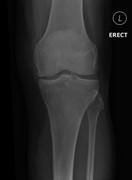

Anterior knee pain: an unusual presentation of renal cell carcinoma

John Broomfield and others

Journal of Surgical Case Reports, Volume 2014, Issue 3, March 2014, rju018, https://doi.org/10.1093/jscr/rju018